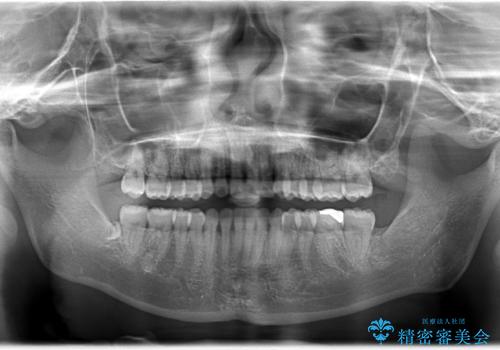

インビザラインによるガタつきの矯正治療 シンプル・短期間

- 20代女性

- invisalign full

- 1年6ヶ月

- 非抜歯、IPR+拡大によるマウスピース矯正を計画した。

一見前歯のガタつきだけのように見えても、そのガタつきの根本的な原因が奥歯の位置であったりすると、マウスピースの枚数がそれなりに多くなり、治療に時間がかかることもあります。